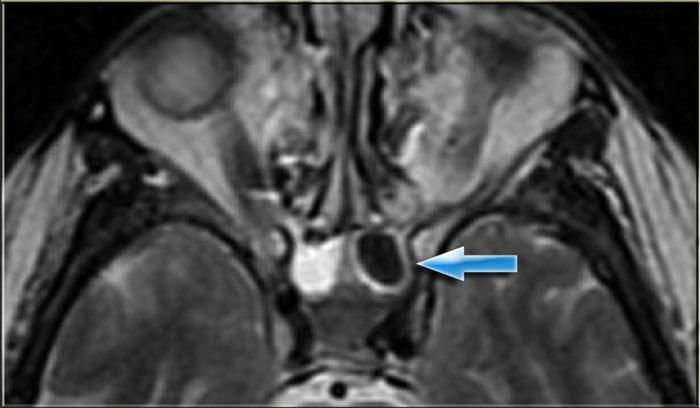

Bên trái là chuỗi xung T1W mặt phẳng axial, bên phải là chuỗi xung T2W mặt phẳng coronal.

Có bất thường ở bên trái, nhưng ở mức độ ít hơn cũng có ở bên phải.

Hãy cố gắng xác định các cấu trúc nào bị tổn thương.

Các mũi tên vàng chỉ vào ống lệ mũi.

Túi lệ kết nối với ống lệ, sau đó dẫn lưu vào ngách mũi dưới.

Bên trái có phù nề mô mềm quanh hốc mắt trước vách ngăn.

Trên hình ảnh coronal, có tín hiệu cao hai bên tại vị trí nối giữa ống lệ mũi và túi lệ, gợi ý ổ dịch.

Bên trái cũng có phù nề mô xung quanh.

Chuỗi xung T1W sau tiêm thuốc tương phản từ, mặt phẳng axial và coronal.

Ở phía ngoài ống lệ mũi hai bên, có các ổ dịch hiện nay cho thấy hình ảnh ngấm thuốc ngoại vi.

Các hình ảnh bổ sung (chuỗi xung T2W) cho thấy bệnh lý niêm mạc xoang hàm phải và mức dịch trong xoang hàm trái, ngoài ra còn có bệnh lý xoang sàng và xoang bướm lan rộng.

Bệnh nhân này bị viêm xoang cấp tính có biến chứng viêm mô tế bào hốc mắt và viêm túi lệ kèm áp xe.

Hẹp ống lệ mũi do bẩm sinh hoặc do viêm là yếu tố nguy cơ dẫn đến viêm túi lệ.